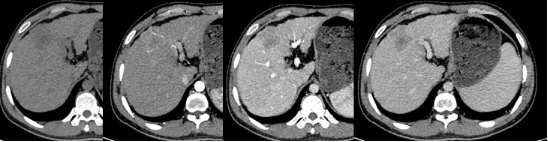

3. 肝脏与胰腺:评估肿瘤的“血供”与关系

肝癌、胰腺癌等:CT和MRI增强扫描是核心手段。通过静脉注射造影剂,并在不同时间点(如动脉期、门静脉期)进行扫描,可以观察肿瘤的血供特点。例如,原发性肝癌通常表现为“快进快出”——在动脉期显著强化(变亮),在门静脉期强化迅速减退(变暗)。这有助于与其他肝脏病变(如血管瘤)相鉴别。同时,影像能精确评估肿瘤与重要血管(如肝门静脉、下腔静脉、肠系膜血管)的关系,判断手术切除的可行性。

图3 CT增强扫描动脉期肝内病灶可见肿瘤血管(箭头处),动态增强扫描呈“快进快出”样强化